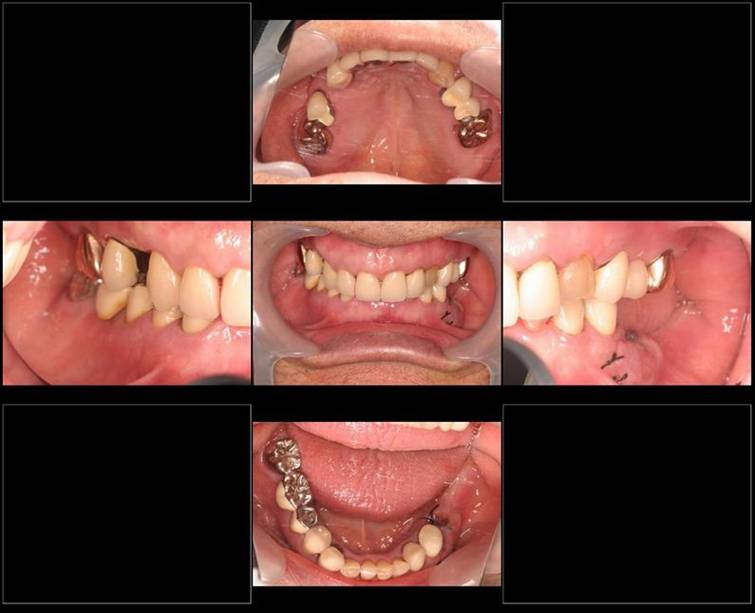

歯周病で抜歯せざるを得ず、インプラントを希望されたケース(使用インプラントはスプライン)

術前。すべての歯が歯周病の末期状態でブリッジ全体がうごいて噛めないとの訴え。右上の犬歯が腫れていました

固定式のブリッジが入っていましたが歯周病で動いています

下顎前歯部には歯石の沈着がみられます

術前パノラマレントゲン写真。根の周りが黒くなり、骨がなくなっていることがわかります